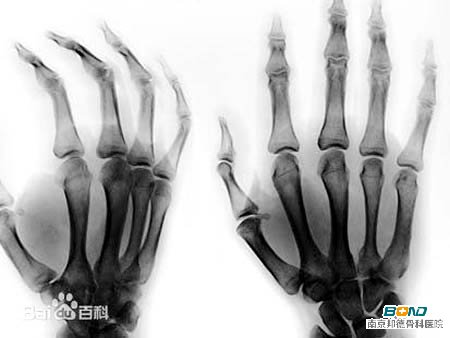

骨性关节炎是一种退行性病变,是由于增龄、肥胖、劳损、创伤、关节先天性异常、关节畸形等诸多因素引起的关节软骨退化损伤、关节边缘和软骨下骨反应性增生。其中,手的骨关节炎是常见的,而且会出现很多的症状表现,给患者带来了一定的影响。手指骨关节炎的主要症状为关节疼痛、僵硬,重者可能出现关节肿胀、肌肉萎缩等。为人熟知的一种特征性改变是在指关节背面的内外侧出现骨性增生而形成的硬结节。 <<<骨性关节炎与类风湿性关节炎有何不同?两者如何鉴别诊断>>>

类风湿性关节炎是一种病因未明的慢性、以炎性滑膜炎为主的系统性疾病。其特征是手、足小关节的多关节、对称性、侵袭性关节炎症,经常伴有关节外器官受累及血清类风湿因子阳性,可以导致关节畸形及功能丧失